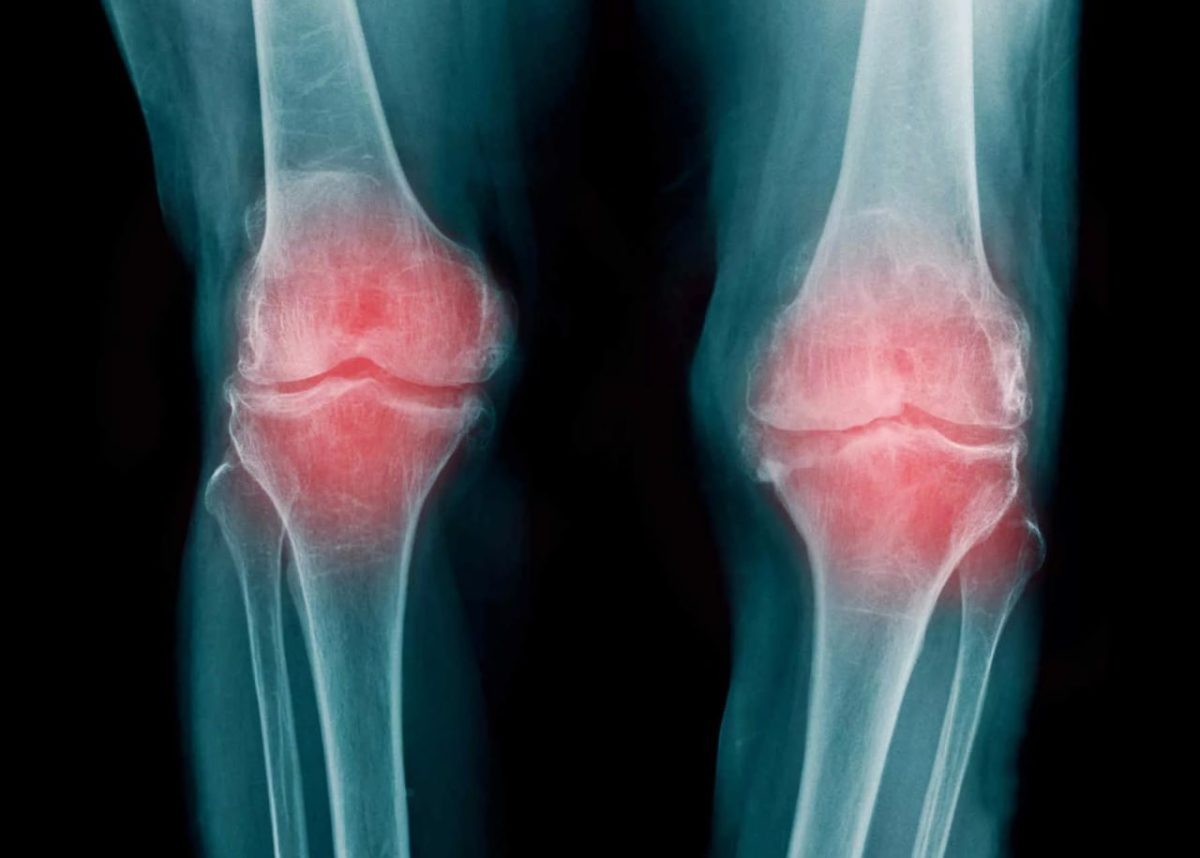

Со временем болезнь перешла на суставы

32-летний мужчина долгое время страдал от псориаза, который со временем перешёл в артрит. Нижегородец попытался лечиться самостоятельно, но это только ухудшило его состояние - он уже не мог двигаться и потерял работу.